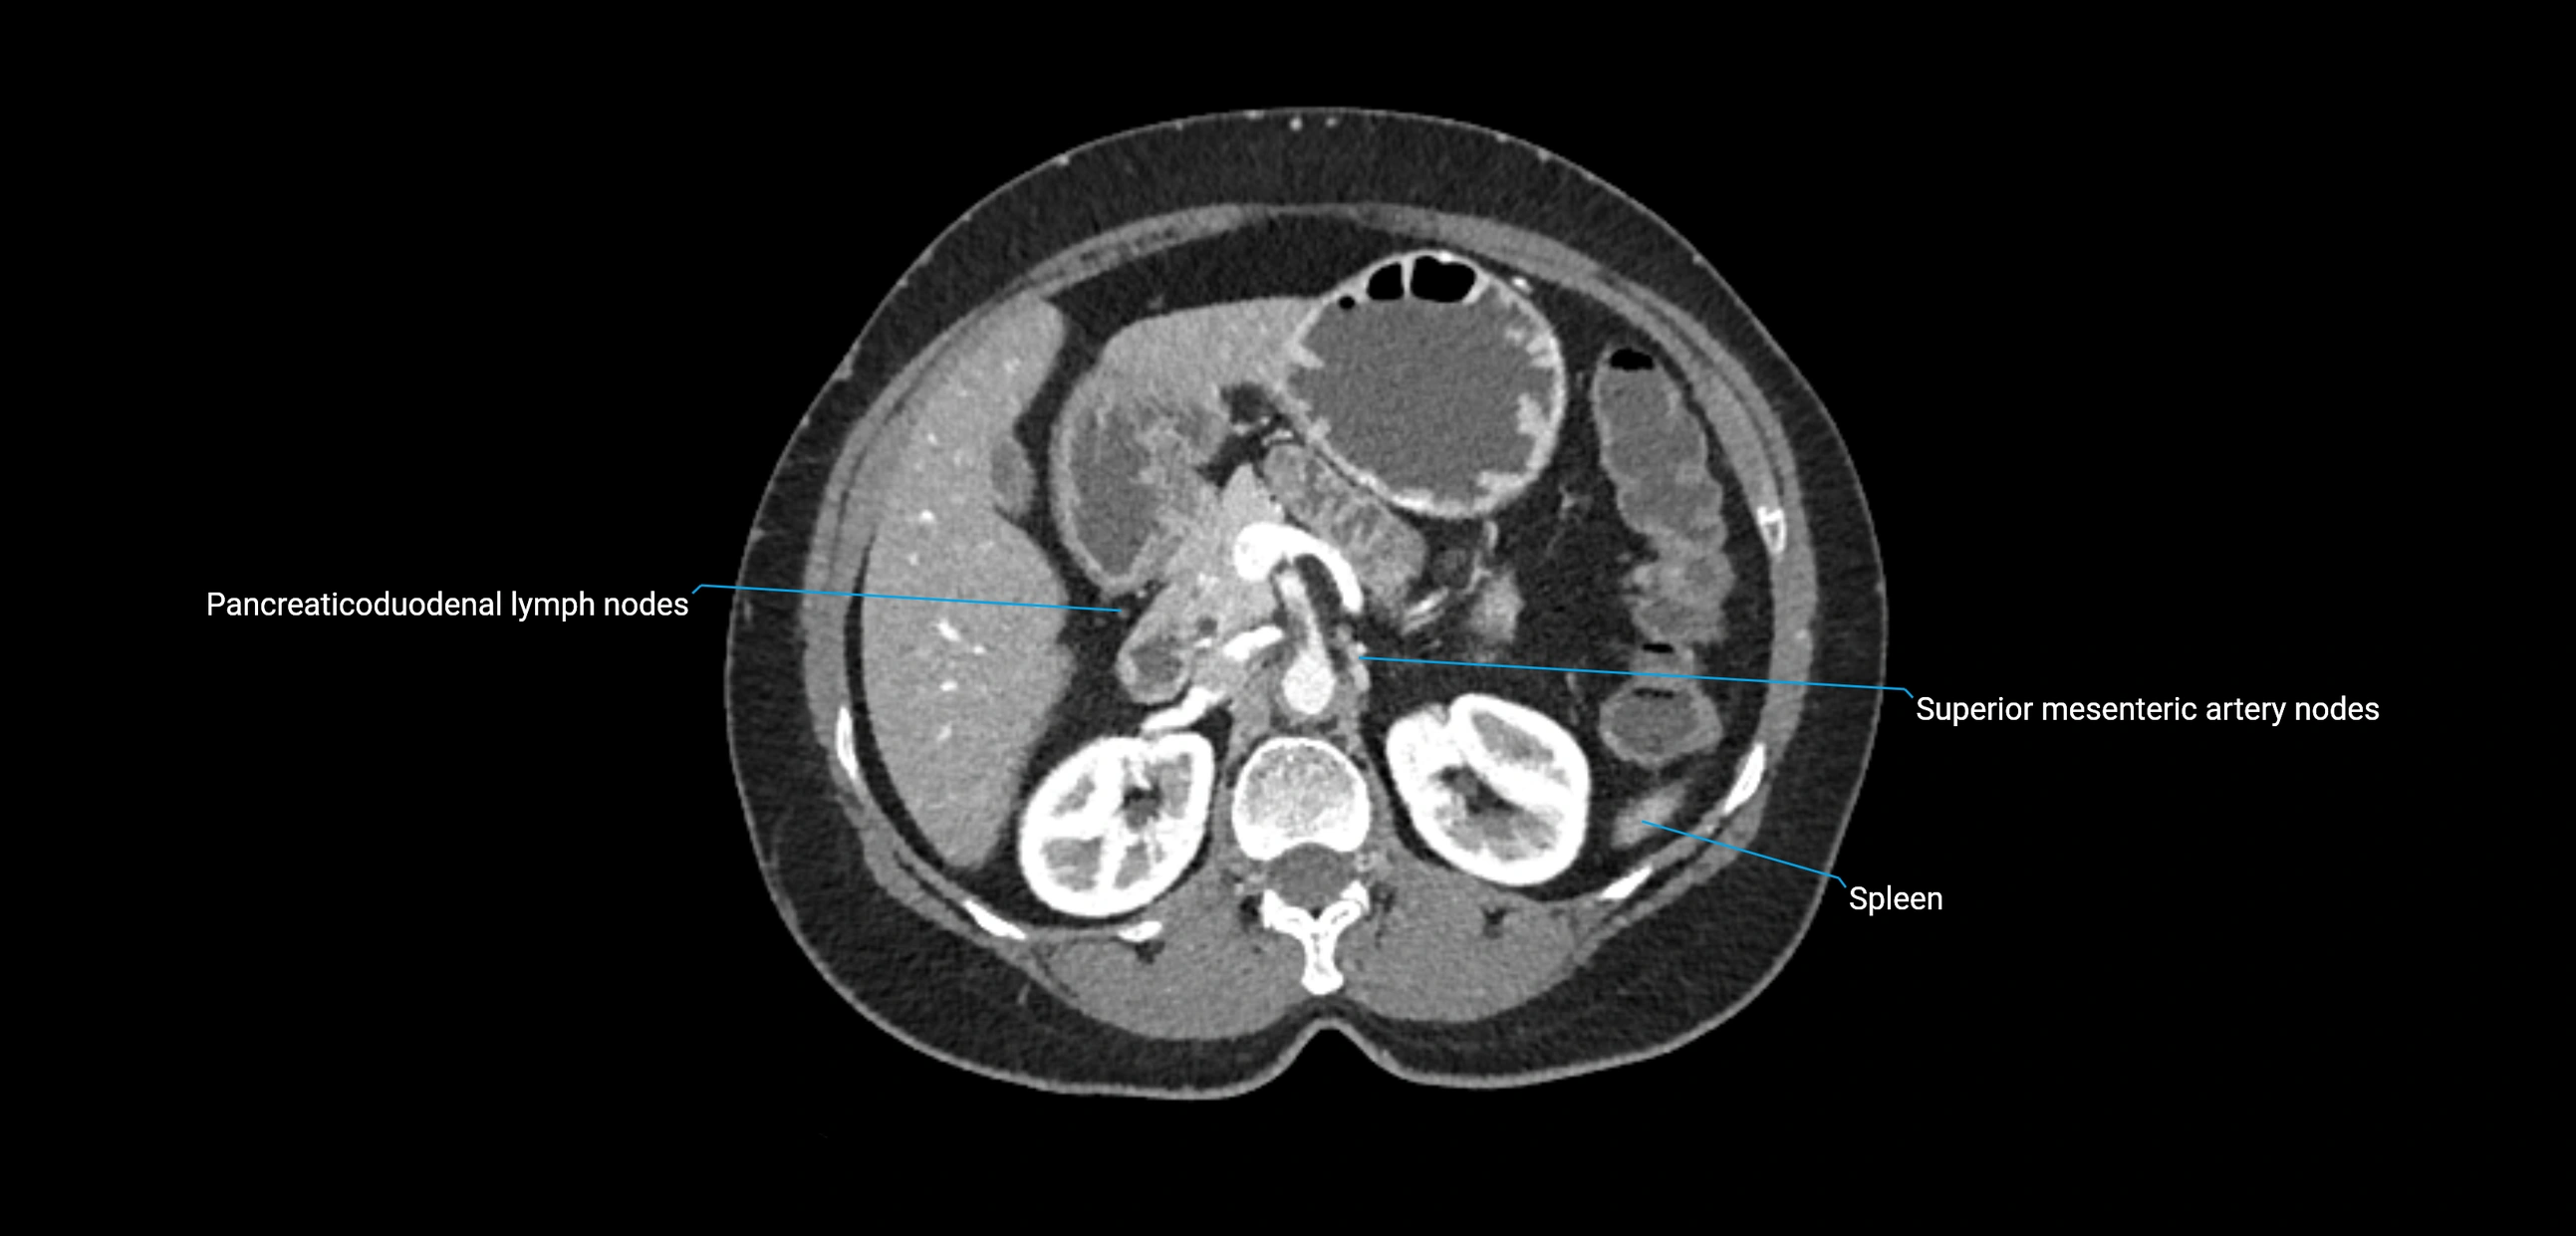

CT Appearance

CT Pre-Contrast:

• Nodes appear as soft-tissue density nodules adjacent to the aorta and IVC

• Calcification may be seen in chronic infections (e.g., tuberculosis)

CT Post-Contrast:

• Normal nodes enhance homogeneously

• Malignant nodes may show heterogeneous enhancement, central necrosis, or conglomerate formation

• Size >1 cm short axis is suspicious, though morphology and distribution are equally important